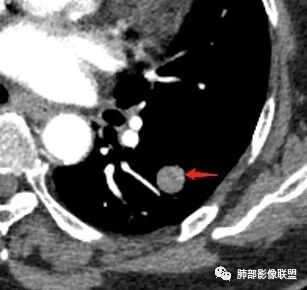

体检患者,左肺下叶结节病灶,病灶形态规则,边界清晰,内部密度不均匀,可见钙化,增强未见明显强化,考虑良性病变,错构瘤可能。

老年女性,体检偶然发现左肺下叶背段实性结节,边缘光滑,无分叶及毛刺,血管贴边,与支气管无明显关系。内密度欠均匀,似有点状稍低密度,增强后轻度强化,综上考虑良性病灶,错构瘤可能,鉴别PSP。

胸CT:左肺下叶背段斜裂旁类圆形孤立实性病灶,边界清晰,密度不均匀,跨度大,内似见脂肪密度,未发现与支气管有关,可见血管贴边,增强呈轻度强化,常规考虑:良性结节,错构瘤可能。鉴别:结核球,周围无卫星灶,无病史,无钙化,不好考虑。其他PSP,类癌,CD等,强化不像。

左肺下叶类圆形结节,边界清晰,密度略欠均匀,隐约见细点状钙化和低密度区,增强动脉期轻度强化,静脉期持续中度强化,血管贴边,首先考虑原发,pSp与错构瘤鉴别,老年女性,孤立结节,转移瘤代排。

●CT上,60%病例可见脂肪密度(CT值-40~-120HU),由于通常含有脂肪、软骨、纤维组织和上皮成分,肿块的CT值离散度大。

●强化方式取决于错构瘤的内部的成份,如果含脂肪及软骨成份较多,血管含量少,血供不丰富,CT增强仅表现为轻度强化或无明显强化;当含平滑肌及腺体成分多时,可出现较明显的强化,但少见。

●错构瘤虽然是良性肿瘤,但有时它也会缓慢生长,逐渐增大,周围血管也会出现推移,所以也会出现“血管贴边征”。